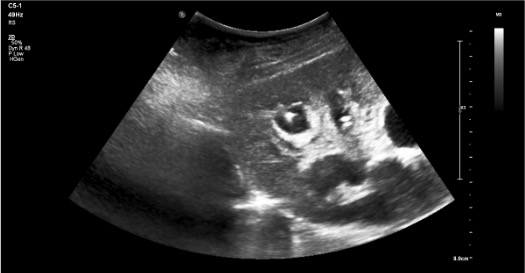

- Positioning and imaging survey — patient prone; US survey to confirm collecting system position, degree of dilation, and select target calyx (posterior lower pole preferred); measure skin-to-collecting system distance

- Calyceal access — advance access needle to target calyx under real-time US guidance; confirm urine return; aspirate and instill equal volume dilute contrast to confirm position and opacify collecting system under fluoroscopy without overdistension (overdistension increases sepsis risk)